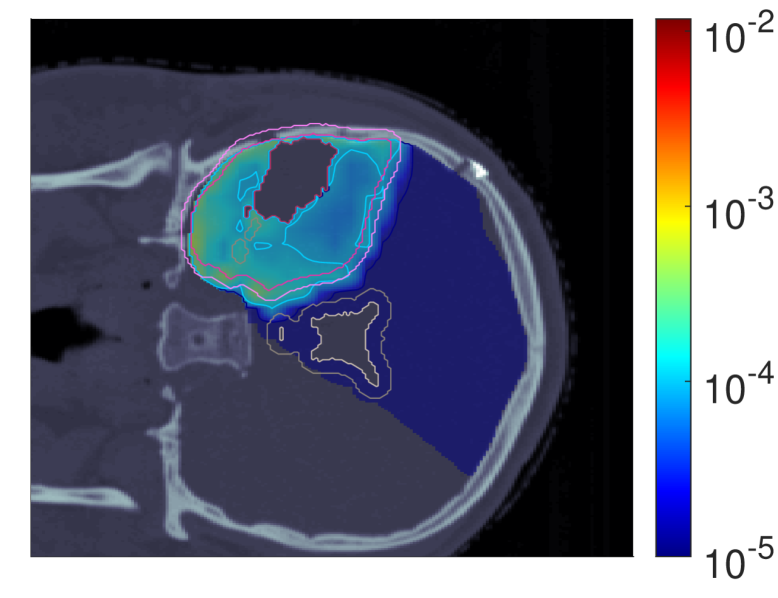

Figure 2 shows the optimal slice images of the dose (left), dose-averaged LET (middle) and POLO distribution (right). On the underlying CT scan, the tumor volumes are marked by violet to purple contours, while the VS (ventricles and 4 mm4\text{\,}\mathrm{mm} fringe) is outlined in white and gray. We observe the high-dose region covering all of the GTV, with a largely homogeneous transition to the clinical and planning target volumes (CTV, PTV), and a moderate to severe overlap to the VS. The dose-averaged LET distributes in layers, with increased values around the contour edge of CTV/PTV and local peaks at the distal ends of the proton beams. Accordingly, hot spots on the POLO map are found in regions where dose and dose-averaged LET scale up, or close to the VS. Beyond the PTV, the POLO map reveals cold spots, due to the steepness of the dose and dose-averaged LET gradients.

dRBE,fxd_{RBE,fx}ABCD ldl_{d}ABCD ppABCD

Refer to caption Refer to caption Refer to caption

NTCP:45.59 %NTCP:$45.59\text{\,}\mathrm{\char 37\relax}$ABCD

Figure 2: Optimal 2D slice images of the RBE-weighted fractional dose dRBE,fxd_{RBE,fx}, the dose-averaged linear energy transfer ldl_{d} and the probability function values pip_{i} for the baseline plan. The dose distribution (left) shows high target coverage with decreasing exposure beyond the CTV/PTV margins, but also visibly overlaps with parts of the VS. Meanwhile, for the dose-averaged LET (middle), layered homogeneity in the target volumes and local maxima at the distal ends of the proton beams can be observed. This results in more pronounced levels of POLO values within the target volumes, particularly in the presence of local dose-averaged LET maxima and in the environment of the VS. Referring back to the POLO model from Equation 1 and (3), we can expect exactly this type of coherence between the model output, the physical input feature profiles and the increased local risk near the VS. The baseline treatment plan exhibits a complication risk of 45.59 %45.59\text{\,}\mathrm{\char 37\relax} after evaluation of the POLO distribution with NTCPpNTCP_{p}.